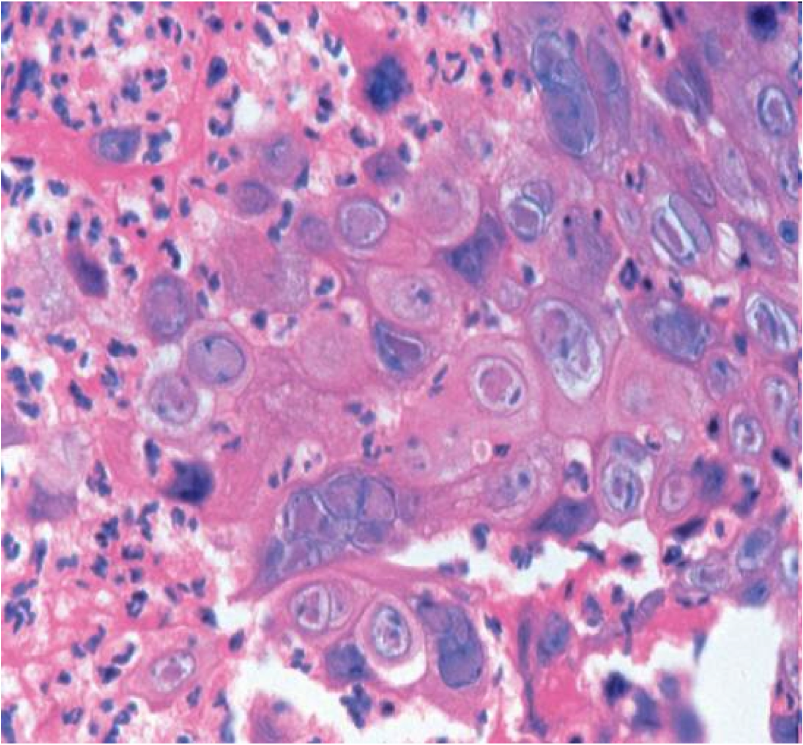

herpes esophagitis

lateral margin of ulcer

cowdry A intranuclear inclusions (Multinucleation, chromatin Margination, nuclear Molding)

CMV esophagitis

- Base of ulcer

- Lg intranuclear inclusion with granular cytoplasmic inclusions

Candida esophagitis

- Immunosuppressed, Diabetics, recent Abx

- Pseudohyphae